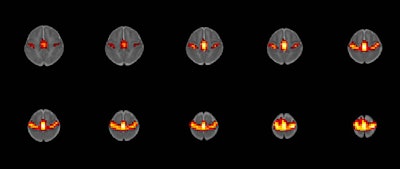

A team of researchers led by Dr. Rupa Radhakrishnan of Indiana University in Indianapolis used resting-state fMRI to study 16 full-term infants. They found that infants with prenatal opioid exposure had significant differences in the way the amygdala connected to various brain regions.

The group of researchers, which included obstetricians, neonatologists, psychologists, and imaging scientists, studied 16 full-term infants -- eight with prenatal opioid exposure and eight without. Anatomical and functional MRI scans were performed on the babies while they were sleeping.

After creating brain maps and applying regions of interest for the left and right amygdala, the researchers found significant differences in the way the amygdala connects to different brain regions.